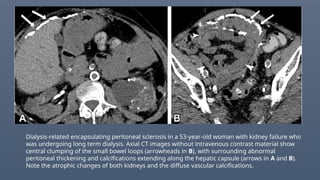

Dialysis-related encapsulating peritoneal sclerosis in a 53-year-old woman with kidney failure who

was undergoing long term dialysis. Axial CT images without intravenous contrast material show

central clumping of the small bowel loops (arrowheads in B), with surrounding abnormal

peritoneal thickening and calcifications extending along the hepatic capsule (arrows in A and B).

Note the atrophic changes of both kidneys and the diffuse vascular calcifications.

Dialysis-related encapsulating peritonealsclerosis in a 53-year-old woman with kidney failure who was undergoing long term dialysis. Axial CT images without intravenous contrast material show central clumping of the small bowel loops (arrowheads in B), with surrounding abnormal peritoneal thickening and calcifications extending along the hepatic capsule (arrows in A and B). Note the atrophic changes of both kidneys and the diffuse vascular calcifications.